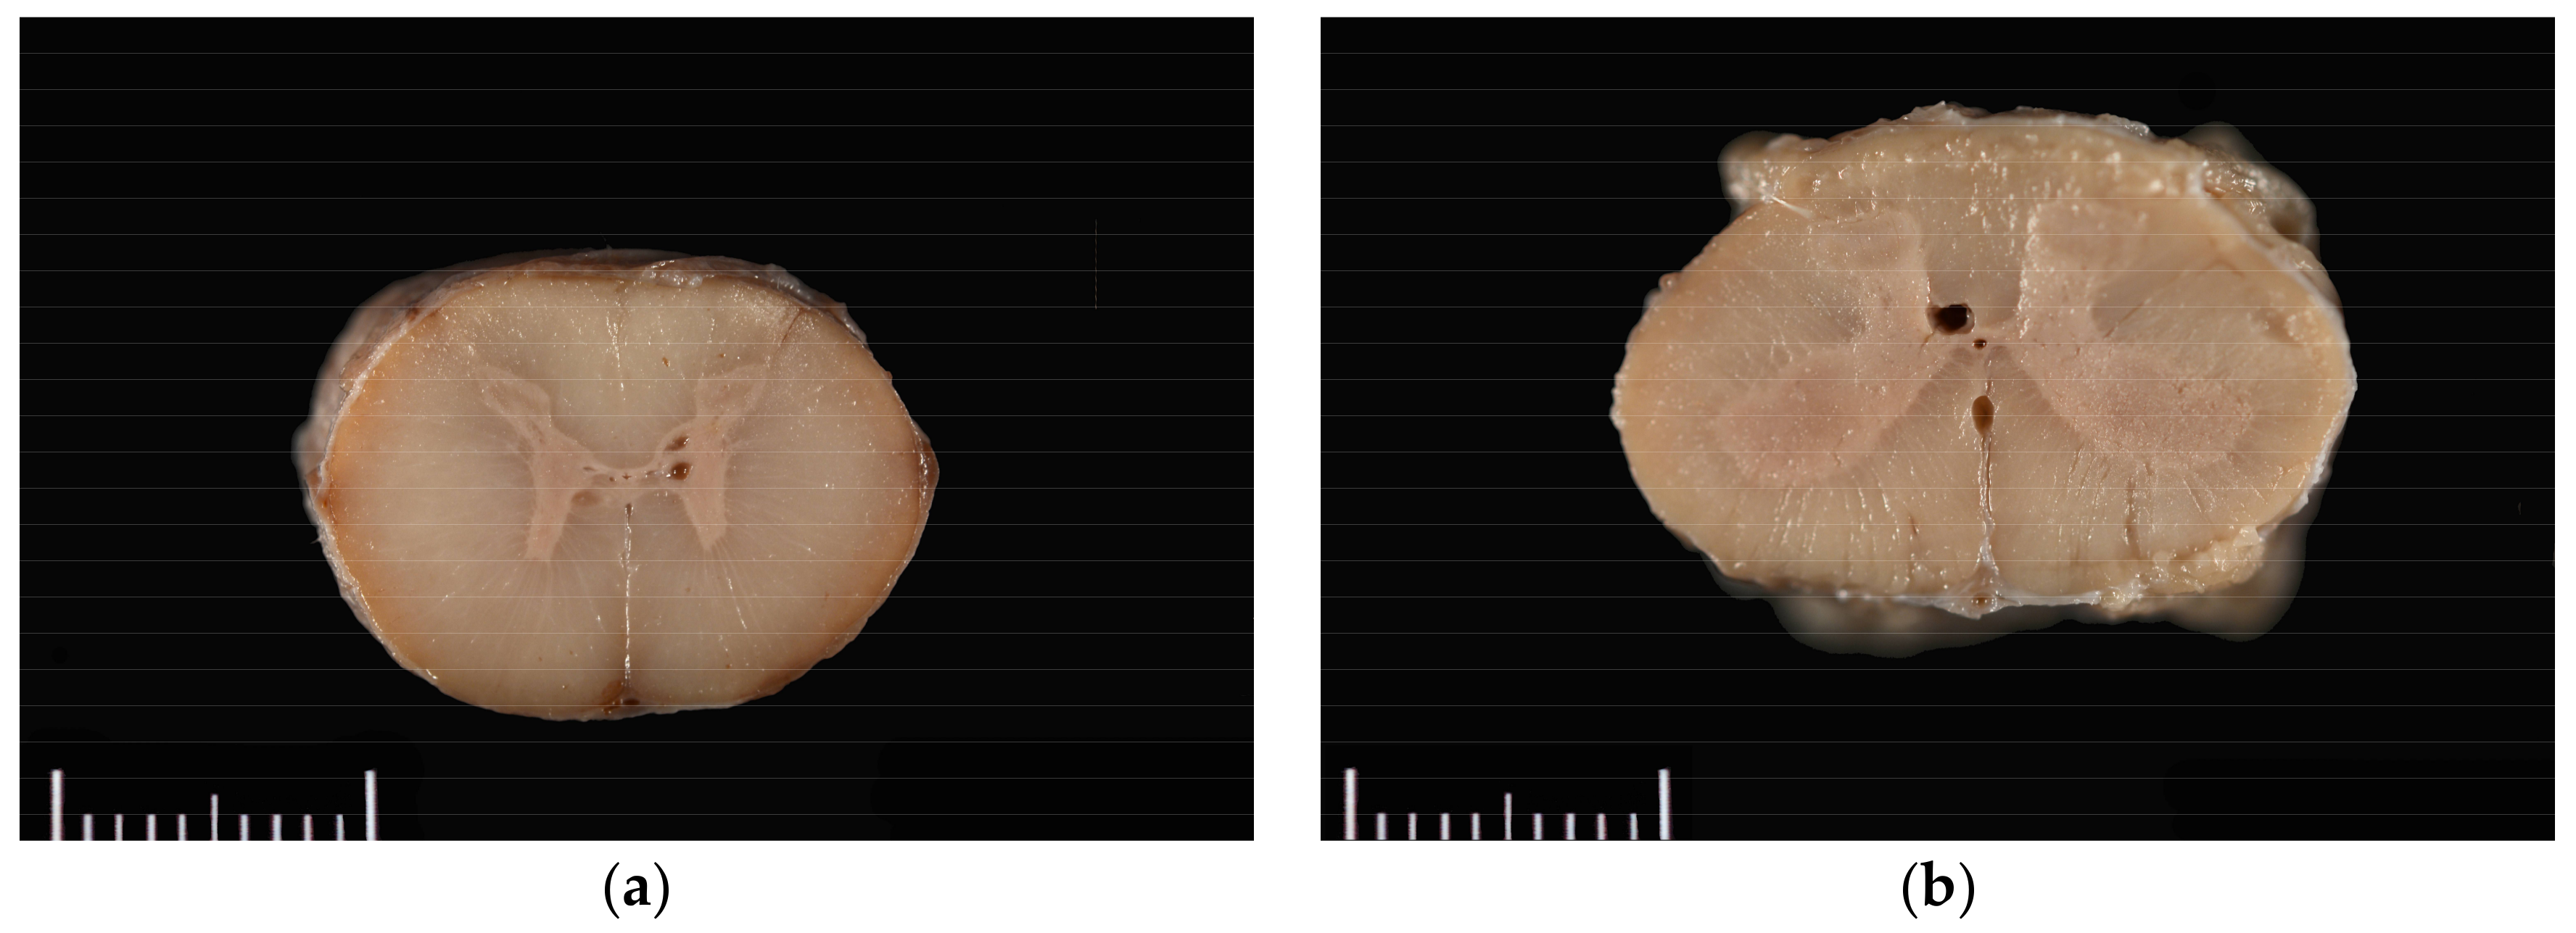

The horse was necropsied at the Utah Veterinary Diagnostic Laboratory. The animal was in good body condition, with adequate musculature and modest subcutaneous and abdominal fat stores (body condition score 4.5/9). Multiple haemorrhages ranging in size from 1.0 × 1.0 × 0.5 cm to 10.0 × 10.0 × 0.5 cm were present in the subcutaneous tissue of the right dorsal and lateral hip, right lateral shoulder, and dorsal head between the pinnae. Upon trimming of the spinal cord after formalin fixation and at histologic evaluation, syrinxes were detected in the right and/or left grey commissures at C5–C6, T7, L1, and L4–L5; and in a lateral horn only at C5 and T14–T15. Syrinxes ranged in size from 125 µm to 2 mm diameter (L5) and consisted of non-communicating, empty cavities bordered by thin rims of compressed grey matter (Figure 1). No communication of the cavities with the central canal was detected grossly. No evidence of axonal degeneration, neuronal degeneration or necrosis, or inflammation was detected histopathologically.

Figure 1. Grossly visible syrinxes within the grey commissures of the spinal cord at the level of (a) C5 and (b) L4.